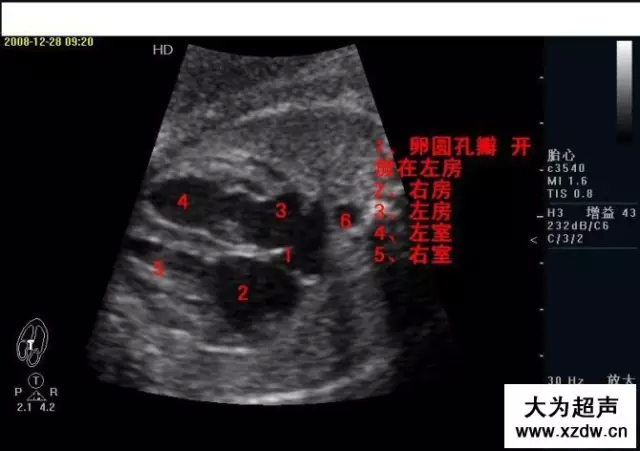

產(chǎn)科超聲正常圖片